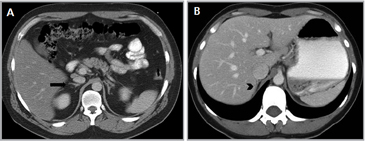

En la TC no contrastada las glándulas suprarrenales normales son homogéneas y simétricas, con una densidad muy similar a la del parénquima renal adyacente (Figura 1 a). Con un medio de contraste ev la glándula suprarrenal se opacifica en forma homogénea, similar al hígado o al bazo (Figura 1 b). Si la cantidad de tejido adiposo retroperitoneal es abundante las glándulas suprarrenales pueden aparecer enteramente rodeadas por grasa y su delimitación es más fácil (Figura 2 a); lo inverso ocurre en pacientes muy delgados con escasa grasa retroperitoneal (Figura 2 b). En RM, en secuencias ponderadas en T1 y T2 convencionales tienen una intensidad de señal homogénea, hipointensa respecto de la grasa adyacente e iso o hipointensa con respecto del parénquima hepático (Figura 3 a y b). En los cortes coronales se aprecia mejor la forma y la posición de las glándulas suprarrenales (Figura 3 c).

Figura 1. Glándula suprarrenal normal en tomografía computada. Cortes axiales de tomografía computada, donde se identifica la morfología normal de la glándula suprarrenal derecha (flecha) en fase no contrastada (a), y tras el uso de medio de contraste endovenoso (b).